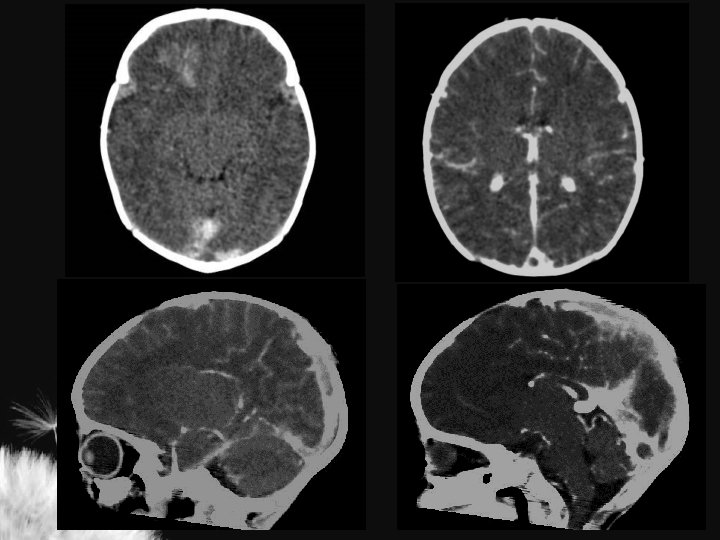

LESÃO HIPÓXICO-ISQUÊMICA NO RN TERMO